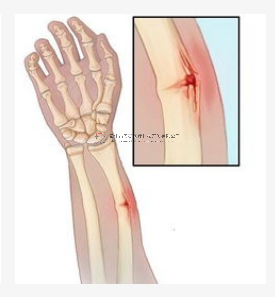

中國接骨學(CO接骨術)(ChineseOsteosynthesis ,CO)中西醫結合治療骨折稱之中國接骨學是中醫骨傷科骨折治療技術的核心技術成果。

CO接骨術的治療原理,就是在有限手術配合下,將復雜骨折轉變為簡單骨折,采用非關節外固定使患者早期功能鍛煉。這一轉變使CO系統由原始無血療法向有血療法轉變。

這也是從傳統中醫正骨的活血化瘀,去瘀生新,動靜結合,筋骨并重;骨肉相連,筋可束骨,祛腐生肌,煨膿長肉等思想逐漸發展起來的。

日前,CO接骨術也在多位前輩的引領下,不斷走向臨床應用,變得成熟。五研醫療也在不斷將外固定支架逐漸推廣,向著智能化方向不斷前進,不斷更新迭代。

目前,五研醫療第二代中醫智能接骨手術機器人準備臨床實驗!投入制作中醫現代化裝備,來更好地服務于廣大骨折患者,引領中醫技術向著更高的方向發展!